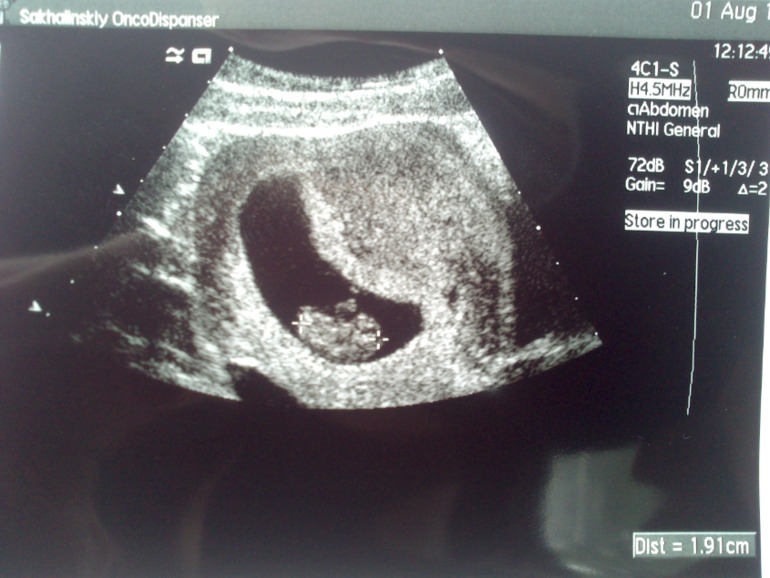

первое плановое УЗИ. УЗИ

УЗИ на 10 недельке

Узистка сказала, что нам 9. У меня с самого начала разница с акушерскими чуть ли не 3 недели! Будем дальше расти)

Толи овуляция поздняя случилась, толи прикреплялся долго. У меня тест бледно-розовую показал на 4 дз и хгч был низкий, а увеличивался потом очень хорошо. Лялька у меня специфическая)

с учетом поздней О, отлично все!!! мы в 9 и 4 27 мм....так то вы в 9 20...все нормуль! не переживай!!! а у тебя по задней прикрепился?

все наверное детишки разные, вот мы в 8 недель были уже 2 см, но думаю это не показательчто что то не нормально или наоборот)))главное сердечко бьется и хорошо))